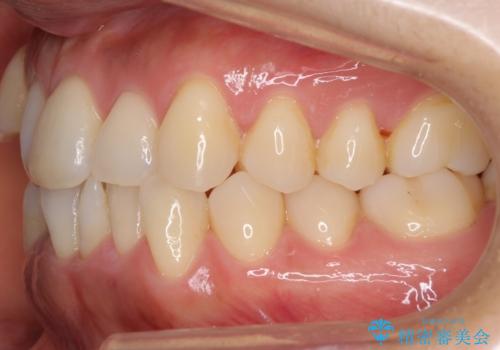

八重歯 上下の正中のずれ 40代で抜歯矯正

- 八重歯と上下の正中のずれを気にして来院。

上の前歯の正中が右にずれていました。

小臼歯抜歯を行い、ワイヤー矯正を行いました。

時間はかかりましたがしっかり治療することができました。